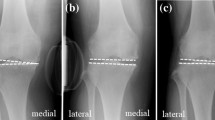

Varus and valgus laxity of the knee in extension (0°), mid-flexion (30°) and flexion (90°) was assessed on radiographs with the use of a custom-made stress device to stress the knee (Fig. 1). Knee laxity was defined as the joint opening under standardized applied moment. The assessments were similar to the method published by Heesterbeek et al. [9]. During the stress radiographs, the subject was in a supine position on a table with the lower leg on a platform with the knee consecutively extended (but unlocked), flexed in 30° and flexed in 90°, with the leg muscles relaxed. The foot was placed in an ankle–foot orthosis. To minimize femur movement when applying torques to the knee, the upper leg was strapped on a thigh support on the medial and lateral sides just proximal to the femoral epicondyles. With the use of 50 N on a pulley 0.30 m distally from the joint line, an external moment of 15 Nm was applied at the knee joint laterally and medially, resulting in varus and valgus stress, respectively. An external moment of 15 Nm was gradually applied to the knee in a standardized way, so that the subject could have continuously relaxed muscles. Under stress, low-dose radiographs (Multidiagnost Eleva, Philips, Best, The Netherlands) were obtained in the anteroposterior view. For each subject, nine low-dose radiographs were made with varus, valgus and no stress (neutral situation) applied, under fluoroscopic guidance with the roentgen ray direction parallel to the tibia joint surface, centred on the middle of the femorotibial joint space.

Varus and valgus knee laxity calculation

The angle between a tangent line on the femur condyles and a line through the deepest tibial joint surfaces was measured on the varus stress, valgus stress and neutral radiographs (Fig. 2). The measurement tool within the radiographic database program (Volume Vision within IntelliSpace PACS Enterprise version 4.4, Philips, Foster City, United States) was used, and measurements were made to the nearest 0.1°. Varus laxity was defined as the difference between the varus stress situation and the neutral situation and valgus laxity, as the difference between the valgus stress situation and the neutral situation [9]. The measurements were performed by a single person (MtM). Duplicates of 25% of the measurements were performed by a second rater (PH), to calculate inter-rater reproducibility. Intra-rater reproducibility was measured with an interval of 4 weeks. Four difficult measurements caused by low-quality radiographs were discussed and scored by consensus of the two raters. For two subjects, the radiographs in 90° flexion were considered to be of insufficient quality, making measurements impossible. These measurements were withdrawn from the data set. Inter- and intra-rater comparisons showed adequate reproducibility for measuring varus and valgus laxity in extension, mid-flexion and flexion in healthy subjects (95% prediction limits (Bland and Altman)) (Table 3). The repeatability of varus-valgus laxity measurements was investigated earlier by Heesterbeek et al. [9] and showed values ranging between 0.6° and 0.9°.